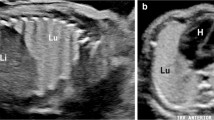

Imaging in a 13-day-old boy with known left-lower-lobe lesion prenatally and incidental imaging of pulmonary sequestration on a spine MRI. a Anteroposterior chest radiograph shows an ill-defined medial left-lower-lobe density. T9 vertebral anomaly (arrow) led to spine MR for evaluation of possible associated cord abnormality. b Axial T2-weighted MR image of lung bases from spine MR shows anterior saturation band to enhance spine imaging. There is a nonaerated, moderately vascular and somewhat T2-bright lesion in the posteromedial left lower lobe, with systemic arterial supply (dark-blood sequence) from the lower thoracic aorta (solid arrow) and venous drainage toward a systemic vein (dashed arrow), consistent with an extralobar pulmonary sequestration. SPLN spleen. c Coronal T2-weighted image from spine MR demonstrates the triangular medial left-lower-lobe nonaerated sequestration. In addition to central dark branching vessels, there is a bright central branching structure (arrow) within the sequestration from mucoid impaction in bronchi, consistent with associated bronchial atresia. Note the absence of the left kidney, with bowel in the left renal fossa